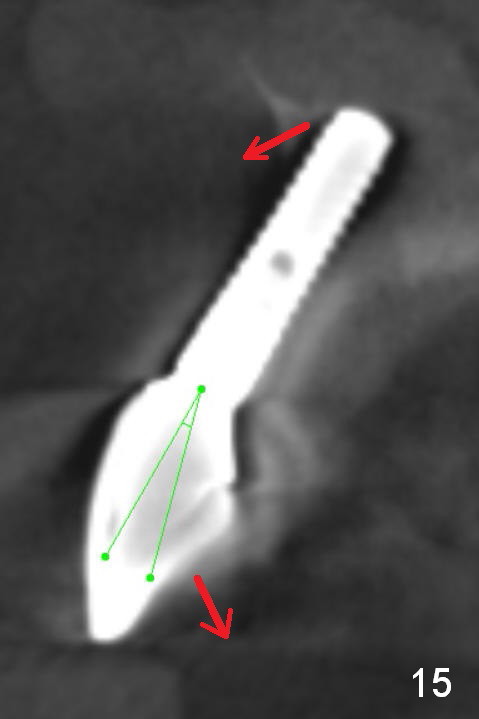

Fig.10 is a sagittal section of the implant (arrowheads: nasal floor). It is apparent that there is enough space (Fig.11,12 (PA)) for osteotomy (Fig.13 red lines: A: angled Titanium abutment). With the palatal mucoperiosteal flap attached the implant/bone segment, it is moved apically (Fig.14). Coronally the coronal portion is repositioned palatally while the apical portion buccally (Fig.15 arrows). Is the segment stable?

It appears that there is not enough bone left for a new implant to be placed if the existing one is to be removed (Fig.3,5,15). What is the most likely to be seen at surgery?